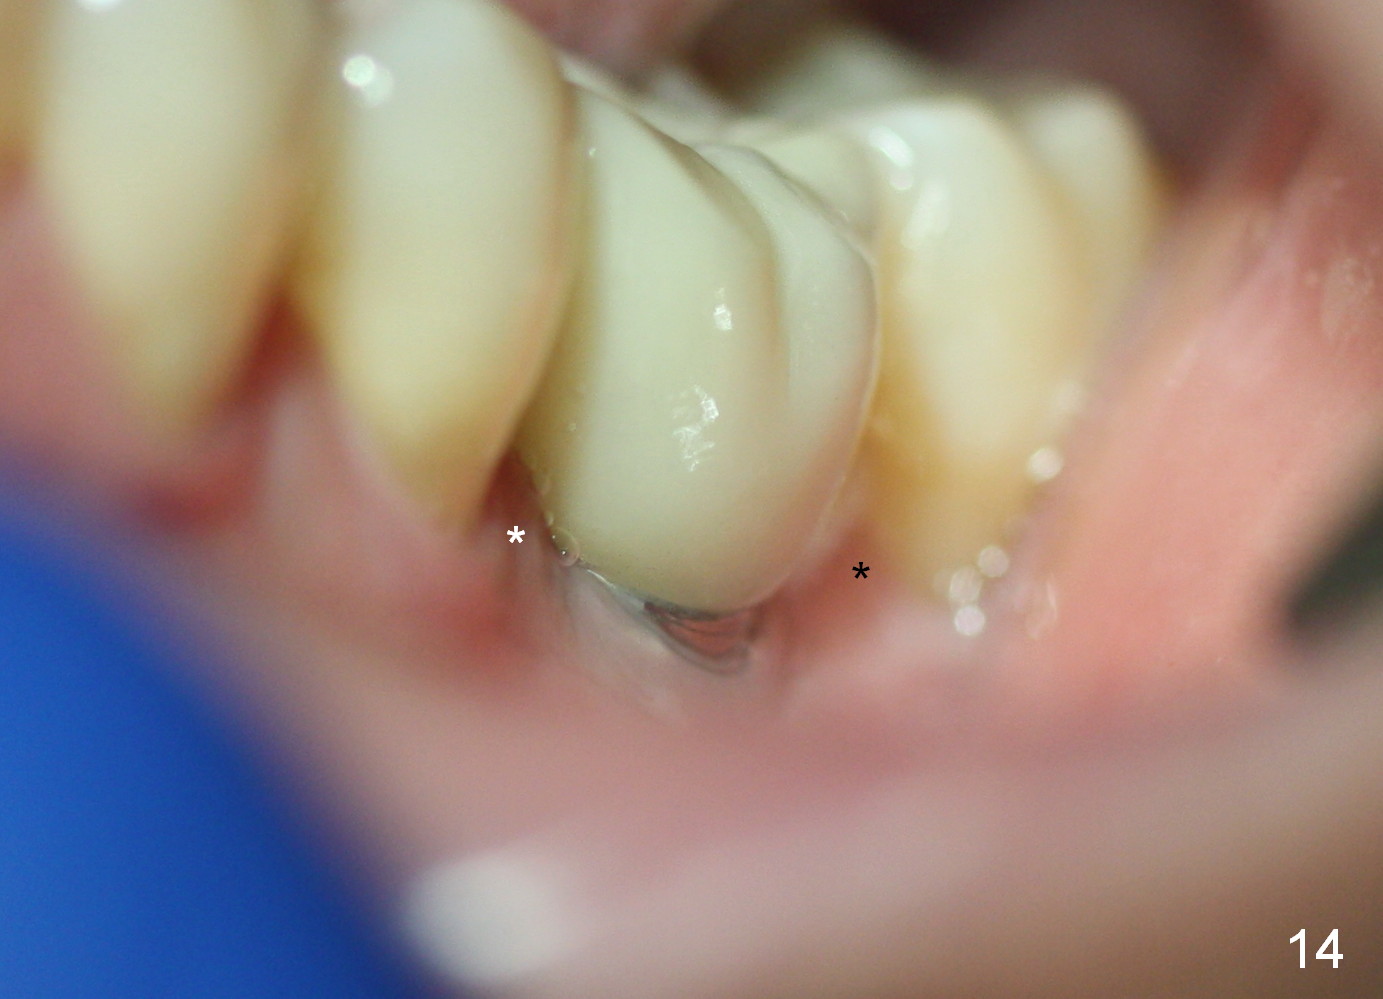

Two and a half months post cementation, the buccal metal show is much less and confined to the midbuccal portion. It appears that the papillae increase their mesiodistal dimension (data not shown). Bone appears to remain stable over the implant surface 2.5 and 9 months post cementation (Fig.12 >,13). The papillae around the implant crown remain normal 11 months post cementation (Fig.14 *). No bone loss is noticed 26 (Fig.15) or 38 (Fig.16) months post cementation. There is no bone loss around the 7x17 mm tissue-level implant 6 years 8 months post cementation (Fig.17).